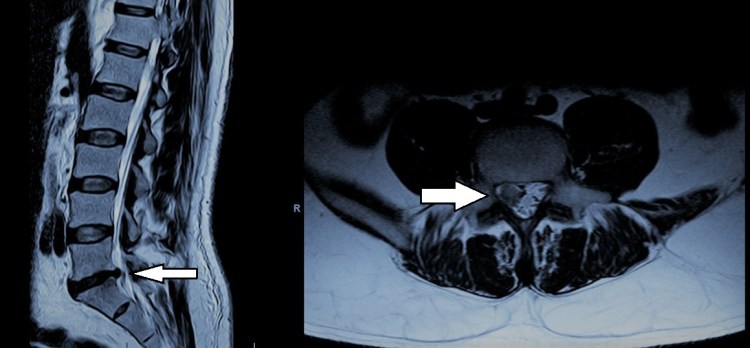

-Hernia discal lumbar: Representa la causa más frecuente de lumbociática en personas entre 20 y 60 años. Se produce debido a la degeneración del disco intervertebral lo que da lugar a una rotura de su anillo fibroso y al desplazamiento posterolateral del material discal que provoca una compresión de las raíces nerviosas que interesan a la extremidad inferior. Nos referimos a protrusión cuando existe un desplazamiento global del disco sin que llegue a tener lugar la herniación del mismo ni la repercusión sobre estructuras nerviosas. Tanto hernias como protrusiones aparecen con mayor frecuencia en los segmentos L4-L5 y L5-S1. La sintomatología típica cuenta con una fase inicial en la que tiene lugar un dolor en la región lumbar que después pasa a irradiarse a una de las extremidades inferiores a través de la región glútea, cara posterior del muslo y cara lateral de la pierna. La sintomatología suele mejorar a lo largo de 6-8 semanas con tratamiento analgésico-antiinflamatorio, calor local y reducción de la actividad (evitando el reposo absoluto). Aquellos casos en los que no existe mejoría debe valorarse la posibilidad de intervención quirúrgica, que en casos adecuadamente seleccionados va a proporcionar una alta tasa de éxito. En raras ocasiones además de la sintomatología descrita puede tener lugar la aparición de vejiga neurógena, paresia severa en la extremidad inferior o dolor incoercible en cuyo caso ha de valorarse la intervención urgente.

-Estenosis de canal (raquiestenosis) lumbar: En estos casos es el estrechamiento global del canal raquídeo lo que condiciona la compresión de las raíces nerviosas que se dirigen a las extremidades inferiores. Aparece sobre todo a nivel L4-L5 seguido de L5-S1 y L3-L4. Tiene lugar fundamentalmente en personas mayores de 60 años y se debe a la progresiva degeneración de las articulaciones y ligamentos que unen las vértebras. Este proceso de desgaste genera un aumento o hipertrofia que deforma dichas estructuras de manera que invaden el espacio destinado a las raíces nerviosas provocando la compresión e irritación de las mismas. Esto se traduce en la aparición de un dolor lumbar irradiado a ambas regiones glúteas y en ocasiones a ambas extremidades inferiores. El dolor se desencadena estando de pie y mejora característicamente al estar sentado pues esta posición ensancha parcialmente el canal raquídeo. Ello da lugar a la denominada “claudicación neurógena de la marcha”, por la cual recorrida una distancia, la persona que sufre de raquiestenosis lumbar tiene que detenerse y sentarse. La distancia a la que aparece la claudicación neurógena va disminuyendo de forma progresiva de manera que los pacientes que sufren este cuadro ven deteriorada su calidad de vida con el tiempo. En estos casos debe valorarse el tratamiento quirúrgico, el cual ofrece un índice de mejoría superior al 90%.

-Estenosis de receso lateral y estenosis foraminal: Se trata de una variante de raquiestenosis lumbar en la que existe una hipertrofia ósea focal que afecta a la zona lateral del canal, de manera que provoca una compresión que en lugar de afectar a todo el conducto raquídeo, afecta a la raíz nerviosa bien en el tramo situado a su salida del saco dural previo a abandonar el conducto raquídeo (estenosis de receso) o bien en el tramo inmediatamente distal (estenosis foraminal). Puede ser uni o bilateral. Sus manifestaciones clínicas son similares a las de la hernia discal. En caso de persistencia de la sintomatología debe valorarse el tratamiento quirúrgico.